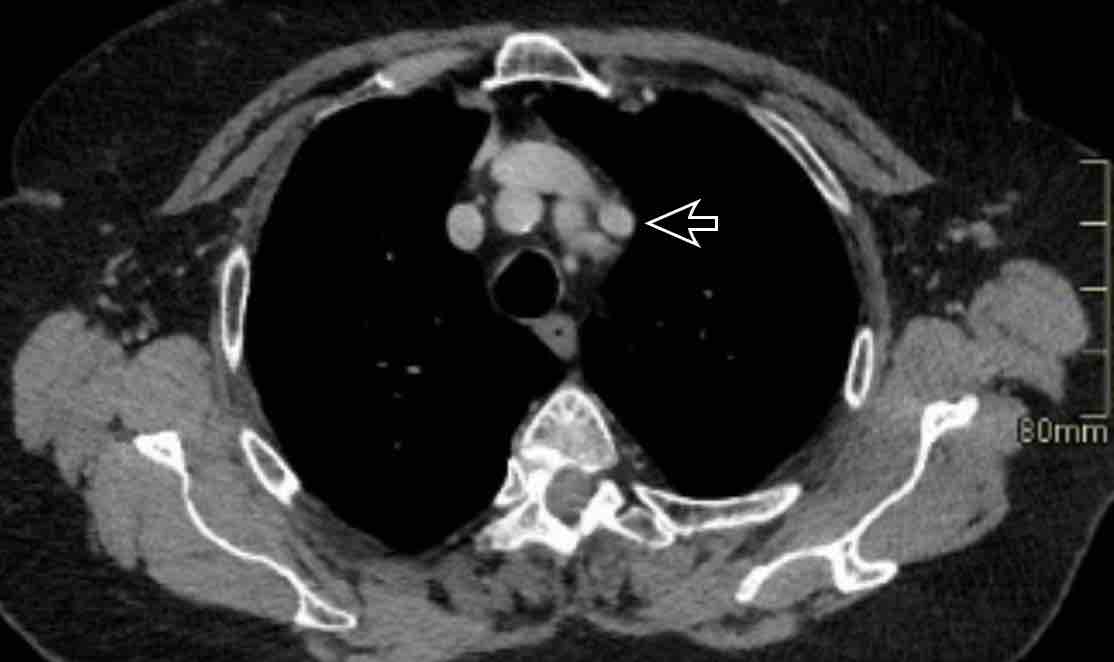

Hình ảnh

Bệnh nhân này được lên kế hoạch cắt thùy trên phải do ung thư phổi và bất thường mạch máu này ban đầu đã bị bỏ sót trên hình ảnh CT.

Những hệ quả trong phẫu thuật của bất thường như vậy nhấn mạnh tầm quan trọng của việc không bỏ sót các biến thể này.

PAPVR bên trái phát hiện tình cờ với dẫn lưu trên tim của máu từ thùy trên trái vào tĩnh mạch tay đầu trái (các mũi tên).